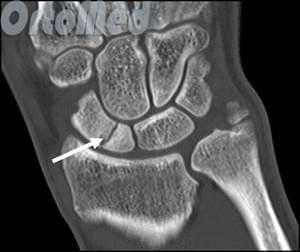

В некоторых случаях, когда по рентгенограмме тяжело определить соотношение отломков назначается компьютерная томография лучезапястного сустава. При таком исследовании можно трехмерно увидеть поврежденную кость, что поможет в определении тактики оперативного лечения перелома.

При выполнении КТ оптимально использовать малый шаг (1,5мм) и делать срезы в плоскости таранно-ладьевидного сустава. КТ часто позволяет выявить неполный перелом, начинающийся проксимально по тыльной поверхности и идущий в косом направлении к дистальной части подошвенной поверхности.

Большой стрелкой обозначен перелом ладьевидной кости, двумя маленькими стрелками – синостоз пяточной и ладьевидной кости.

На основании КТ-картины можно подразделить пациентов на 3 группы, 1 тип - изолированные переломы дорсальной кортикальной пластинки, 2 тип – перелом дорсального кортекса и тела кости, 3 тип – полный перелом ладьевидной кости. Тяжесть течения и сроки сращения увеличиваются соответственно от 1 типа к 3.